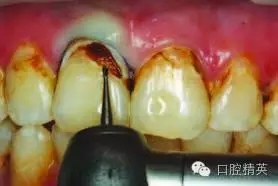

圖3:#6smartburs最先用于去除腐質(zhì)

使用#6 Smartburs II車針( SSWhite)在轉(zhuǎn)速15,000轉(zhuǎn)每分鐘下開始去腐(圖3)。使用該車針去腐至該型號的車針頭部無法進(jìn)入較小的齲壞部位有效去腐(圖4)。